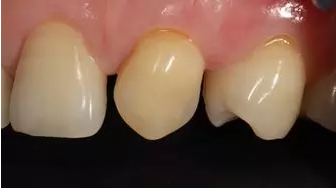

術(shù)后上前牙正面照

術(shù)后上前牙右側(cè)面照

術(shù)后上前牙左側(cè)面照

術(shù)后1周上前牙正面照